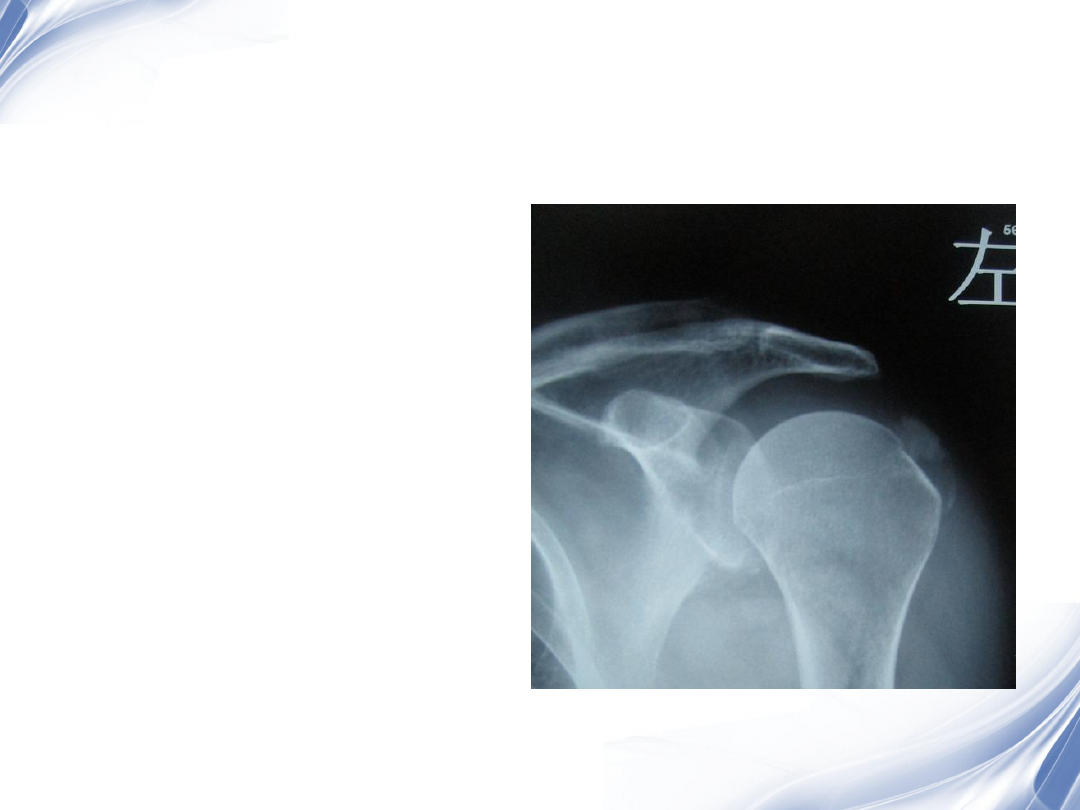

巨大肩袖损伤肩峰下间隙

<9mm